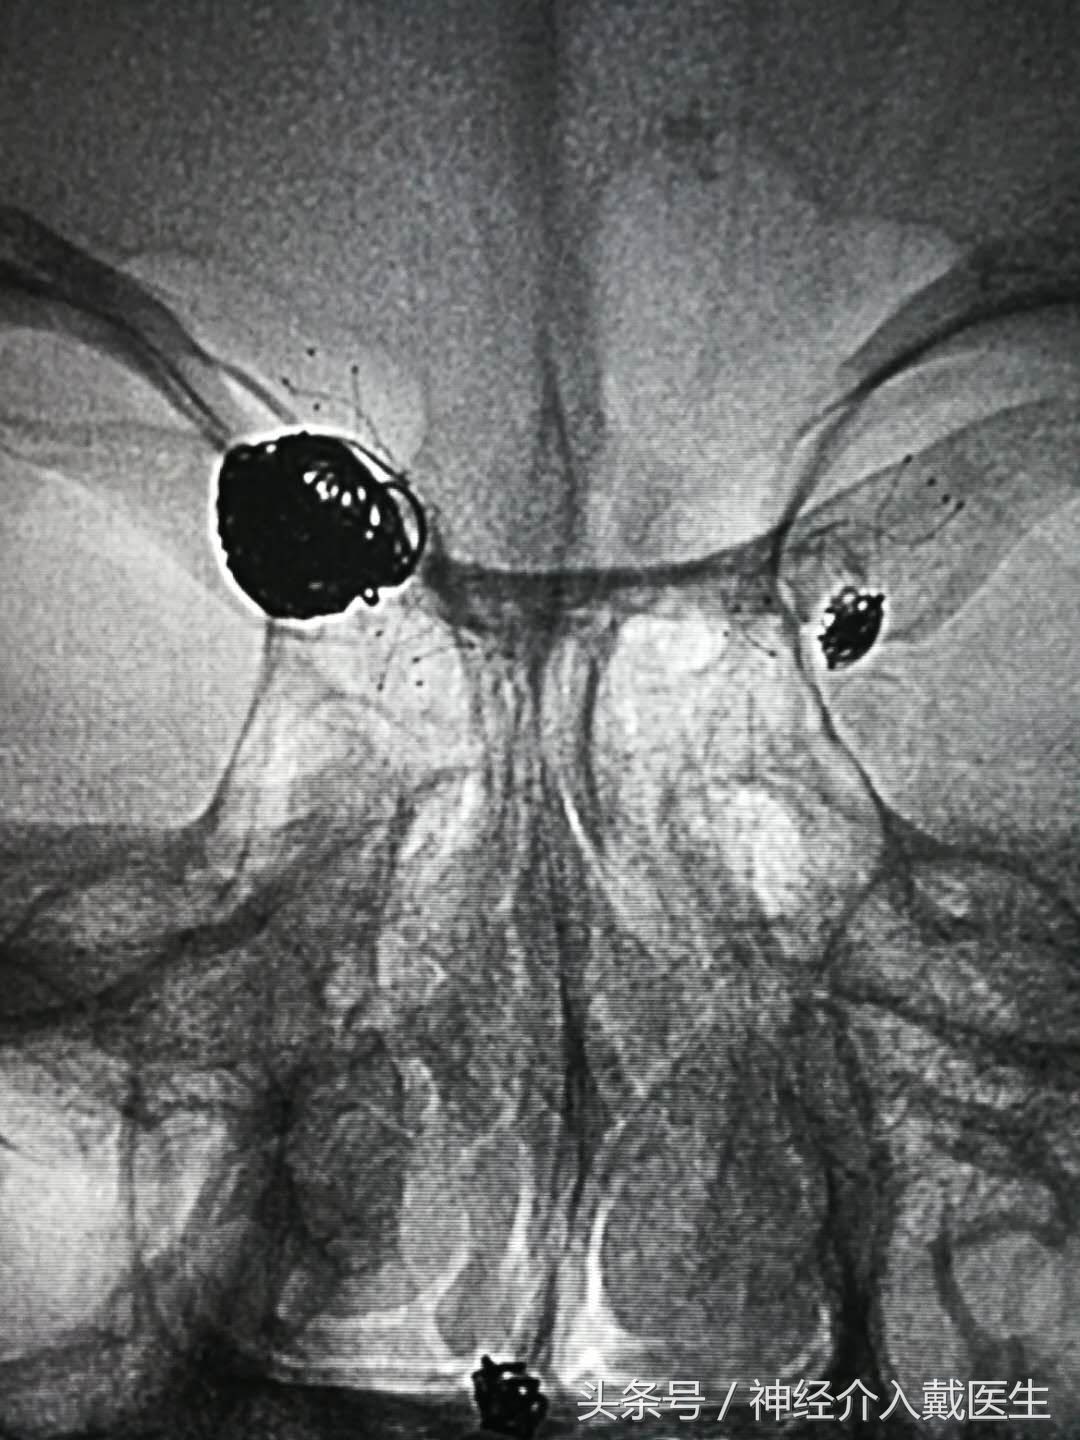

一,颅内动脉瘤辅助栓塞。

对于宽颈,梭形复杂的动脉瘤,如果开颅手术,也是很有难度的,介入栓塞有时可以相对简单,使用支架可以防止弹簧圈突入载瘤动脉,使动脉瘤介入治疗成为可能,

支架辅助弹簧圈动脉瘤栓塞术大大提高了介入治疗的适用症,特别对于超宽颈,夹层,梭形动脉瘤,大大改善了动脉瘤治疗的长期疗效,支架网丝的脚手架作用促进了动脉瘤颈部位的内皮细胞的生长覆盖,促进了瘤颈部位的解剖愈合,另外,支架也改变了载瘤动脉的形态和角度,引起血流动力学的变化而促进动脉瘤的长期愈合,支架的运用改变了动脉瘤治疗的理念,